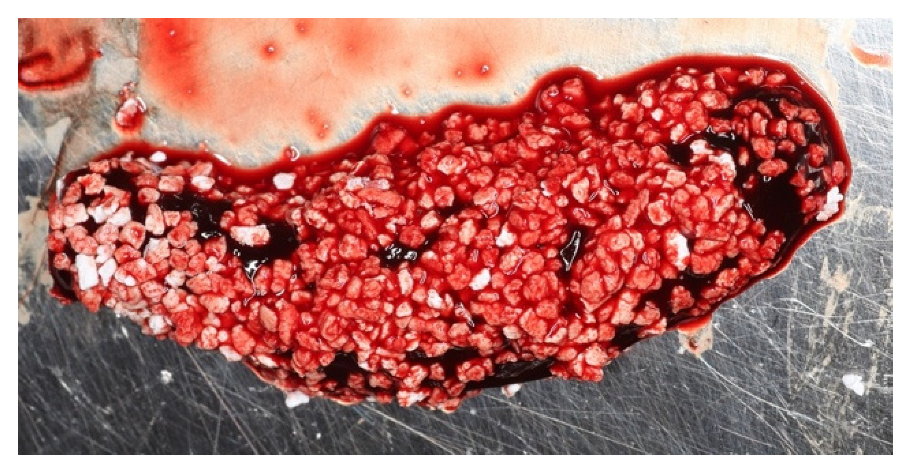

2. The Blood Clot